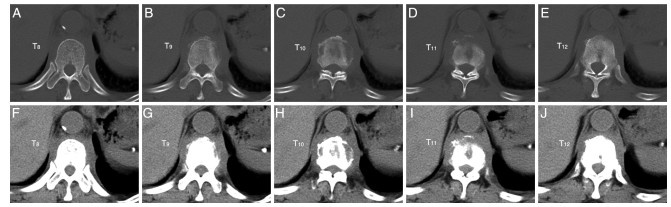

本文报道1例罕见的老年胸椎多发骨嗜酸性肉芽肿(eosinophilic granuloma, EG)病例。患者男性,66岁,因“腰背疼痛伴乏力两年余,加重三个月”就诊。经糖皮质激素联合免疫抑制保守治疗后临床表现及实验室检查好转,病理活检显示肉芽肿组织消失,后因病变部位出现压缩性骨折行外科手术治疗。该病例提示糖皮质激素联合环磷酰胺治疗成人多部位骨嗜酸性肉芽肿患者是可行的。